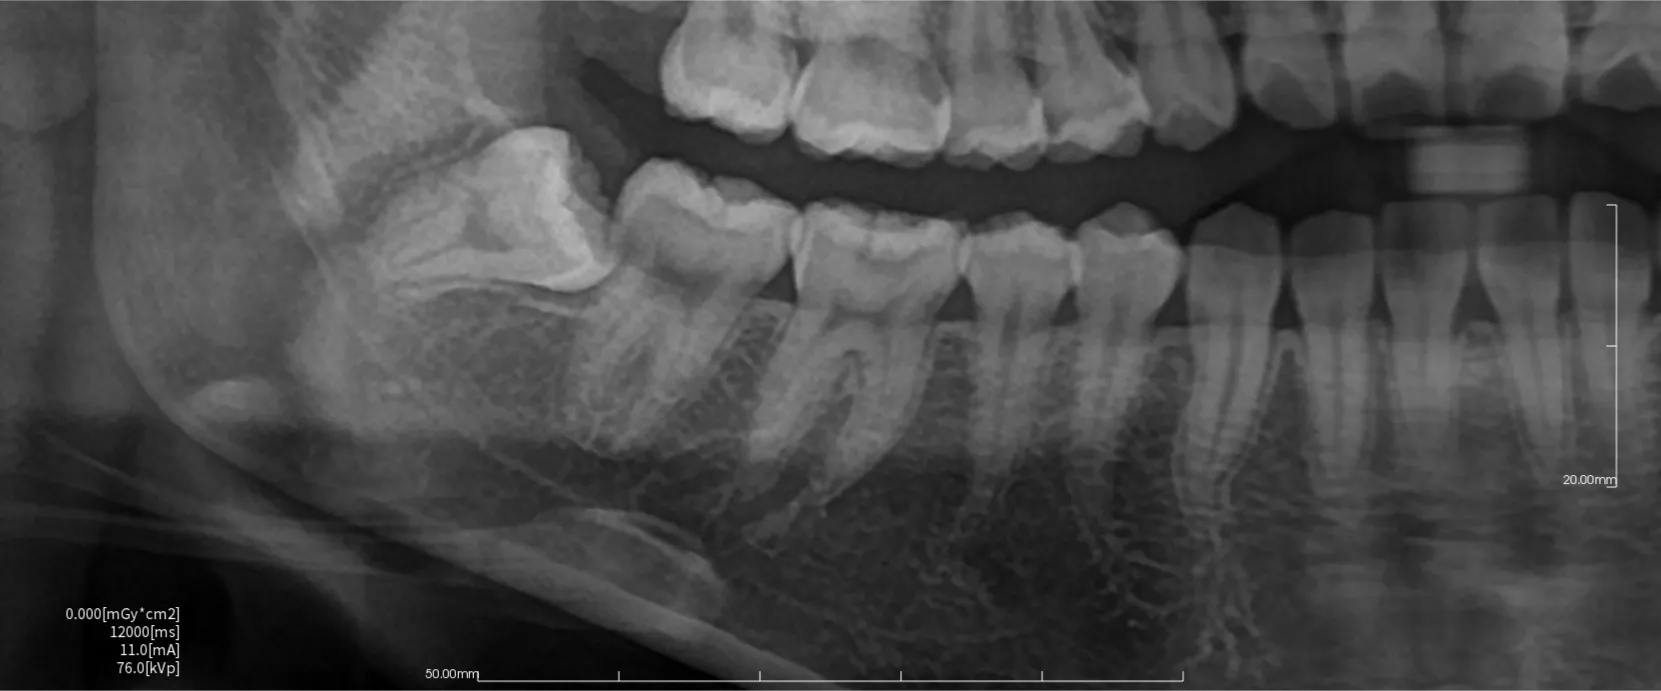

今回は一見問題なく見える歯の詰め物の下に深い虫歯があった治療の症例をご紹介いたします。